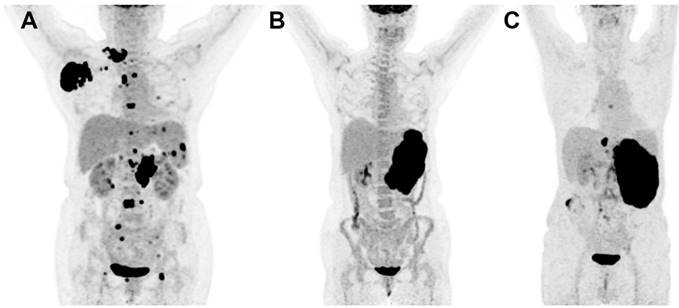

Focal BM uptake was defined as focally increased FDG uptake higher than normal liver FDG uptake (Figure 1A). Diffusely increased FDG uptake was interpreted as diffuse homogenous FDG uptake higher than that of normal liver (Figure 1B). Normal uptake was considered as a mild homogenous uptake lower than that of normal liver (Figure 1C). Structural abnormalities including osteolytic, osteosclerotic lesion, mixed lesions or no abnormalities were observed through CT images.

Figure 1

MIP images of focal (A), diffuse (B) and normal (C) FDG uptake patterns of bone marrow in DLBCL.